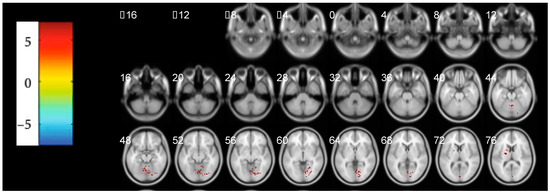

3.2. The Abnormal Activated Brain Regions by mALFF Analysis

| Region Label | Cluster/Voxels | Peak t-Value | Montreal Neurological Institute (MNI) Coordinates | |||

|---|---|---|---|---|---|---|

| x | y | z | ||||

| Positive | Thalamus | 158 | 9.730 | 6 | −21 | 9 |

| Inferior Parietal Lobule | 220 | 10.612 | −45 | −27 | 24 | |

| Cingulate Gyrus | 110 | 7.665 | −6 | −15 | 45 | |

| Publisher’s Note: MDPI stays neutral with regard to jurisdictional claims in published maps and institutional affiliations. |